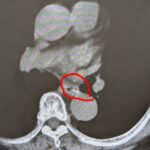

背中が痛い男性

2025年12月2日

総合診療医

60代の男性です。 1か月前から背中が痛くて、近くの整形外科に受診しました。 レントゲンで異常なく、筋肉痛と言われました。 よくならないために、当院に受診し CTをとったところ、右肺に大きな腫瘍を認め、総合病院にご紹介になりました。 背中が痛いのは、整形外科ではなく 総合診療かかりつけ医に受診が必要です。 一番怖い病気をまず否定することを、総合診療かかりつけ医は考えます。 視野広く、診療すること...